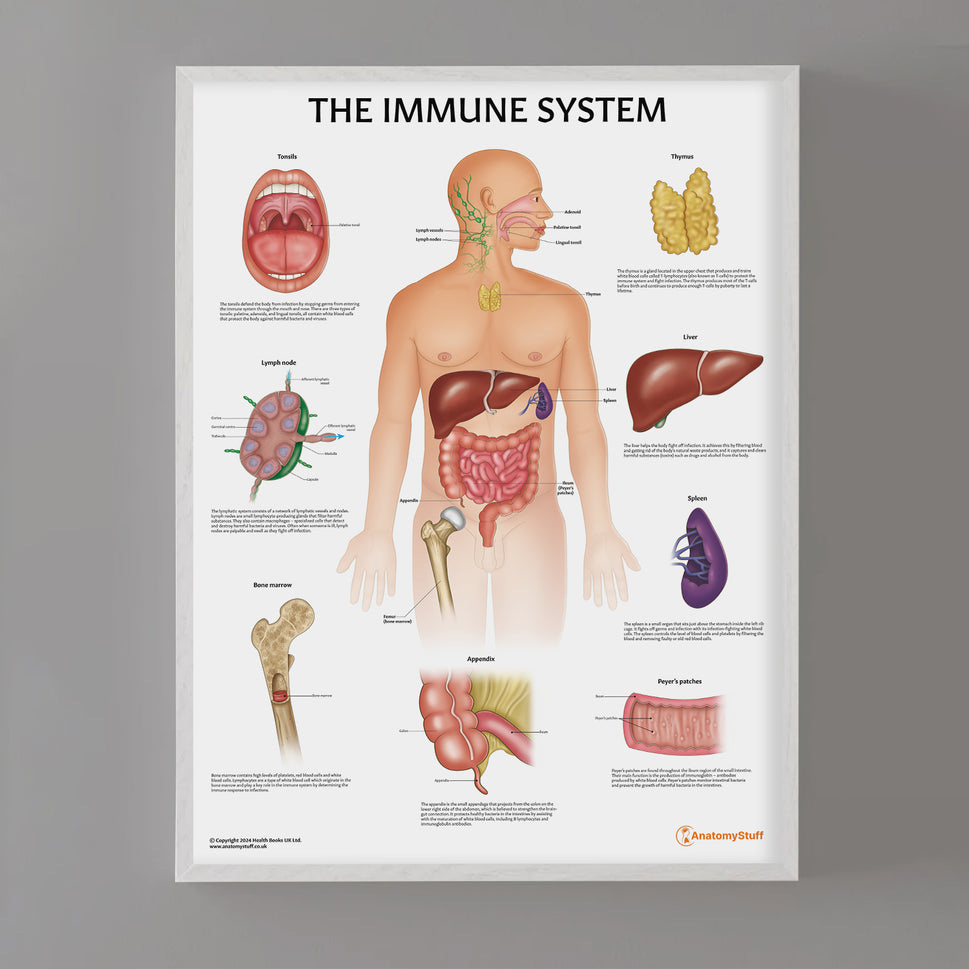

Enhance medical education with our collection of digestive system anatomical models including the stomach, liver, gallbladder, pancreas & colon models. Discover the anatomy of healthy organs as well as common gastrointestinal diseases such as stomach ulcers, gallstones and liver cirrhosis. Our digestive system anatomy posters are ideal for study and patient education.

At AnatomyStuff we stock a diverse range of digestive system anatomical models to suit your training needs. From budget models and affordable medical education posters to highly advanced 3D printed bowel models, you can transform medical training and patient education. As well as our own exclusive collection, we are proud resellers of 3B Scientific, Anatomy Lab, Denoyer-Geppert Science Company, ESP Models, Erler Zimmer and GPI Anatomicals. Explore our exclusive collection of digestive system anatomy charts, posters, fine art prints and digital anatomy study guides. Discover the anatomy of key organs like the liver, stomach, pancreas and bowel as well as the pathophysiology of common conditions like peptic ulcer disease, coeliac disease, IBD and much more. We have anatomy posters suitable for school children all the way up to medical degree level. From a liver anatomy poster to a digital study guide all about common GI disorders, find exactly what you need right here to enhance medical training and patient education.